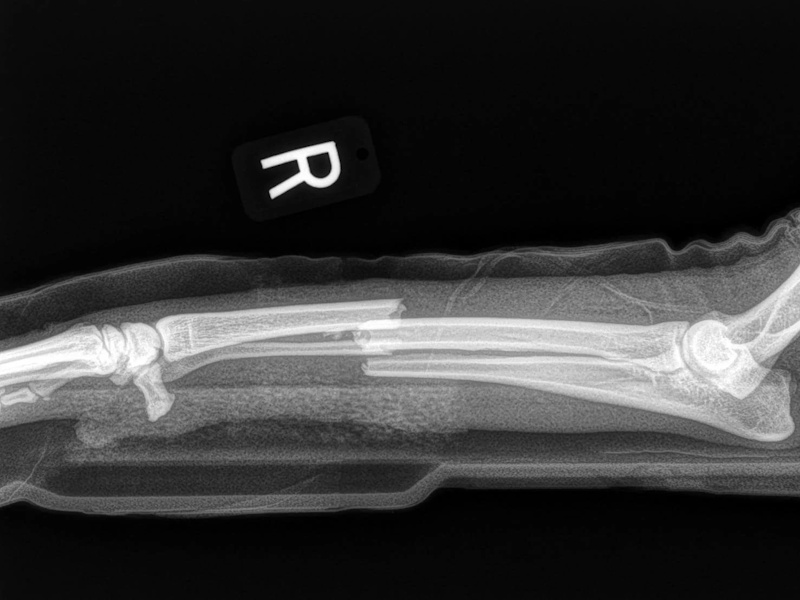

Fore Limb (Humerus, Radius/Ulnar, Metacarpus)

Hind Limb (Pelvis, Femur, Patella, Tibia/Fibula, Lateral Malleolus)

- Fracture Fixation: $4,000 - $8,000+